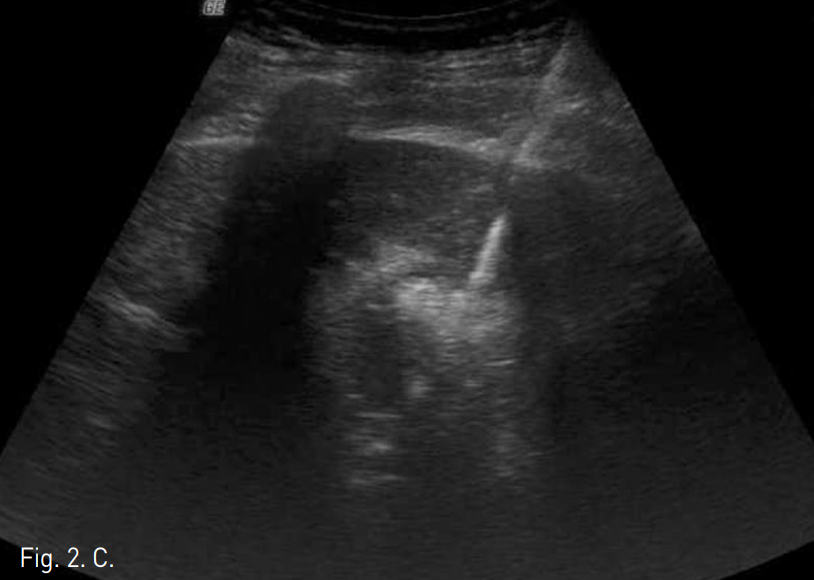

Fig. 2

A. Sonography before PEIT procedure demonstrates the adherence of the gallbladder (arrow) to the S4 HCC (arrow head).

B. Sonographic image taken after PEIT of the S4 HCC. Total 13cc absolute ethanol has been injected at both lateral and inferior aspect of the mass with the remnant portion measured as 1.5x1.8cm (arrow).

C. Sonography during the RFA ablation of the remnant tumor. RFA probe with 2cm ablation tip was used.